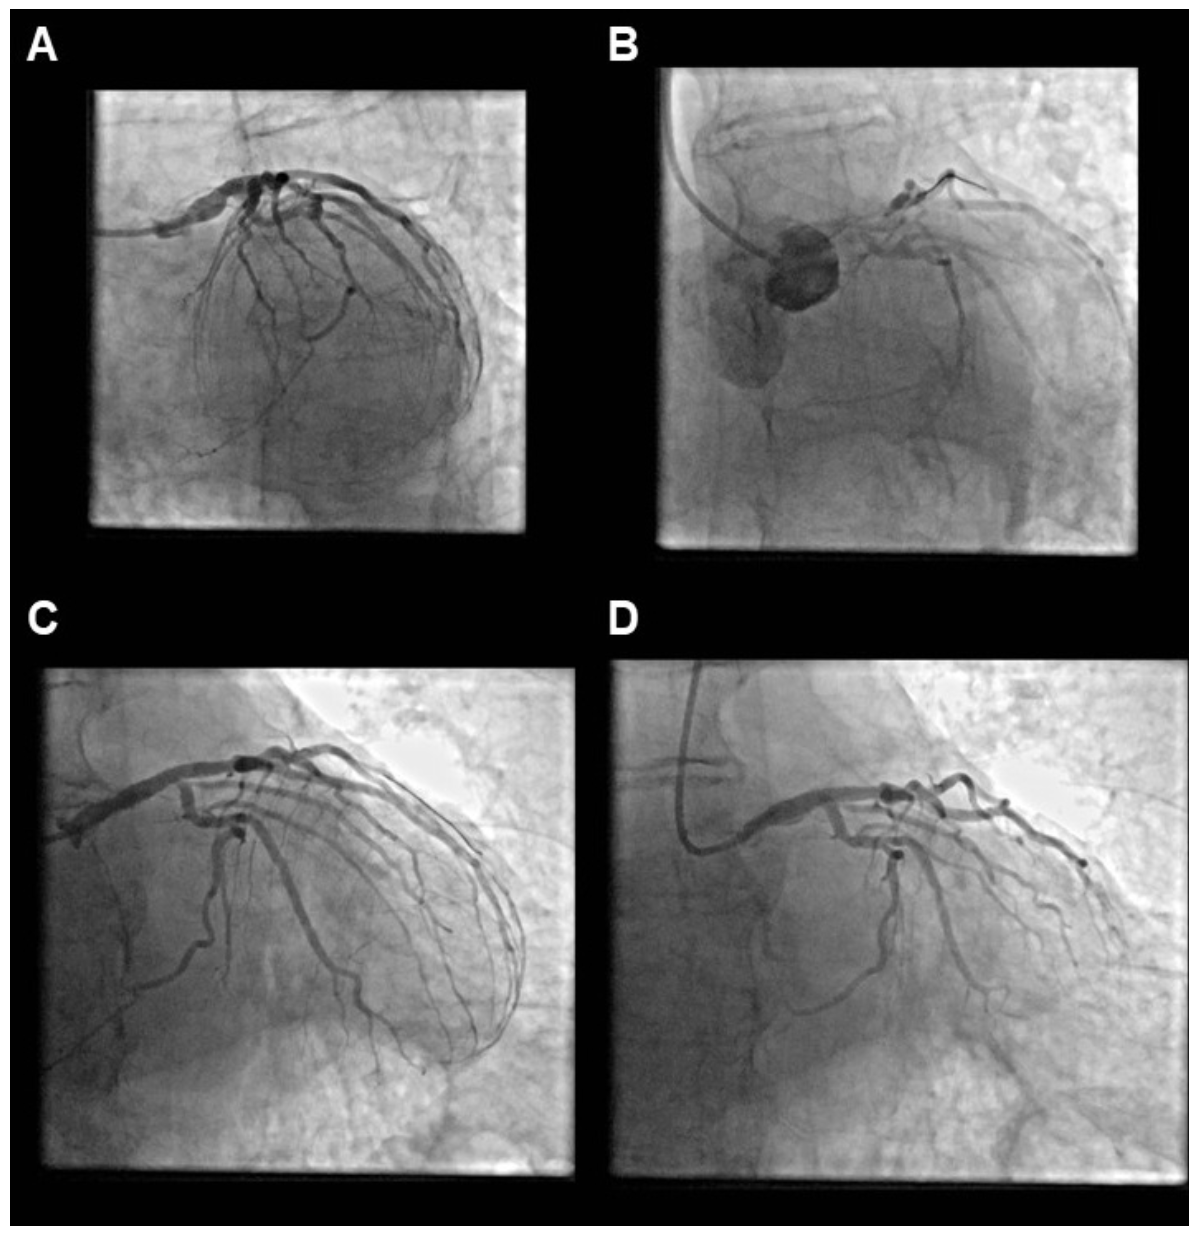

Guide-catheter dissection is seen in <1% of PCI and is associated with deep engagement of large catheters into smaller, diseased arteries.12 In our study, guide-catheter positioning caused the dissection in 18% of the dissection cases (Figures 4 and 5). Amano et al3 examined the incidence and outcomes of guide catheter-induced iatrogenic coronary artery dissection in a study of 77,257 patients and reported an incidence of 0.14%, which is similar to our rate of dissections caused by the guide catheter (0.24%). Hiraide et al10 analyzed data from 17,225 consecutive patients undergoing PCI at 15 hospitals between 2008 and 2016 and reported the incidence, predictors, and in-hospital outcomes of catheter-induced coronary artery dissection. Catheter-induced dissection occurred in 185 patients (1.1%). Similar to our study, catheter-induced dissections was associated with high in-hospital mortality (6.5%) and in-hospital adverse cardiovascular events (14.1%). Patients who experienced catheter-induced dissections with decreased residual flow were at higher risk of postprocedural complications.10